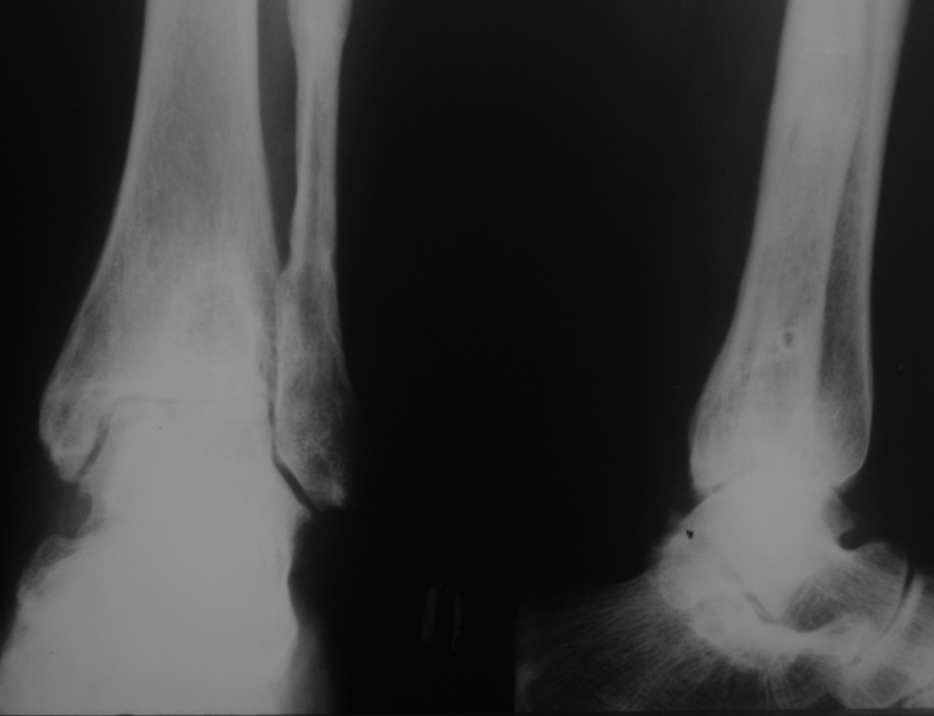

Уважаемые коллеги, разъясните ситуацию.Пациентка, 45лет. 9 месяцев назад произведен синтездвухлодыжечного перелома правой голени.

Конструкции на данный момент удалены. Объем движений на фото. Сейчас беспокоят скованость в области сустава, боли к концу рабочего дня - классическая клиника артроза.Пропила 4 курса найз. Откуда артроз такой выраженности (на рентгенограмме)? Поможет ли консервативное лечение и какое поможет наверняка?

Интересно бы посмотреть операционные снимки и знать сроки иммобилизации, операции по постановке и удалению конструкции и был ли винт в синдесмозе? и когда он удален? когда больная начала давать нагрузку и в боковой проэкции это недостатки обработки рентгенограмм или такой остеопароз.

Артроз, во-первых, вследствие неконгруентности суставных поверхностей - имеется укорочение малоберцовой кости; во-вторых имеется синостозирование берцовых костей (вместо тугоэластисчного синдесмоза).

>Артроз, во-первых, вследствие неконгруентности суставных поверхностей - имеется укорочение малоберцовой

Но укорочение - 3мм, и потом суставная поверхность наружной лодыжки не несет осевой нагрузки

>во-вторых имеется синостозирование берцовых костей (вместо тугоэластисчного синдесмоза).

Даже если это были оригинальные имлантаты "Synthes", то к "АО" этот остеосинтез не имеет ни какого отношения. Потому, что вся философия АО в отношении переломов лодыжек основана на том, что наружная лодыжка это нагружаемая часть сустава, на которую приходится примерно 1\6 веса тела. Восстановление длины м\б кости является приоритетным, и наружную лодыжку называют ключом г\ст сустава.

"Стягивающий винт на синдесмоз" противоречит АО, т.к. этот винт должен быть позиционным и не должен создавать компрессиию на уровне сочленения берцовых костей и между наружной лодыжкой и таранной костью. Стягивающий винт - основная причина синостоза на месте синдесмоза.

этих-то 3 мм и достаточно для формирования артроза. Наружная лодыжка - ключ к голеностопному суставу!